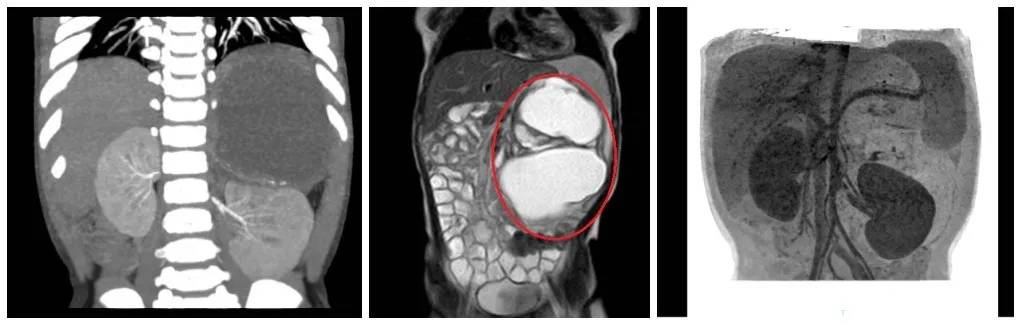

什么是畸胎瘤 畸胎瘤是人体幼稚生殖细胞发生变异而形成的肿瘤,常发生在卵巢,其次是在睾丸,此外还可以发生在纵隔、骶尾部、腹膜后等部位。 畸胎瘤的瘤体内可见皮脂、毛发、骨头、软骨甚至牙齿、眼珠,肌肉、脑等组织。由于这些组织成分与人体正常组织成分十分相似,有点像发育畸形的“胎儿”,故此得名。 “年龄这么小,却在腹膜长了这么大一个畸胎瘤,这样的病例是非常罕见的。”柳州市妇幼保健院小儿外科副主任欧阳昱安慰慧慧妈妈,畸胎瘤良性率为90%,但在发现后应该尽快切除,否则随着年龄的增长,转为恶性的几率会逐渐提高。 “慧慧的肿瘤很大,已经占据了腹腔很多空间,如不及时处理,会压迫邻近脏器。如瘤体压近消化道会出现肠梗阻;推挤膈肌会出现呼吸困难;如与消化道相通时可出现瘘,瘤体还可发生感染引起感染症状。”欧阳昱副主任告诉慧慧妈妈。听了专家的中肯建议后,慧慧妈妈同意尽快给孩子做手术。 ▲ 肿瘤挤压腹腔脏器移位